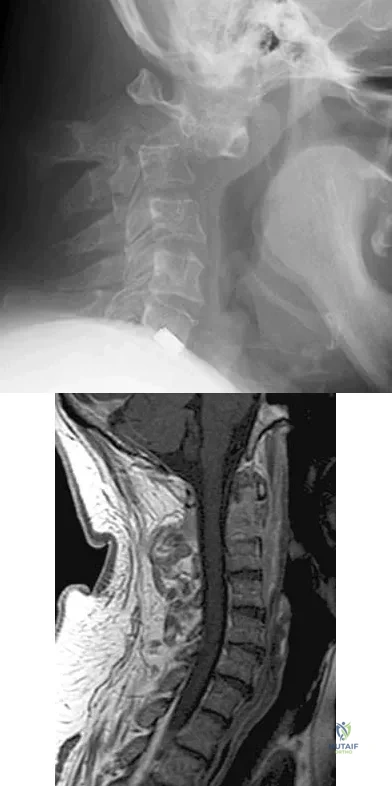

Figure 7 shows the radiograph of a 64-year-old man who has neck pain and weakness of the upper and lower extremities following a motor vehicle accident. Examination reveals 3/5 quadriceps and 4/5 hip flexors but no ankle dorsiflexion or plantar flexion. His intrinsics are 1/5, with finger flexors of 3/5. He is awake, alert, and cooperative. Management should consist of

Explanation

Question 40

Figures 5a and 5b show the radiograph and MRI scan of a patient who has severe mechanical neck pain but no neurologic problems. Biopsy and work-up show the lesion to be a solitary plasmacytoma. Treatment should consist of

Explanation